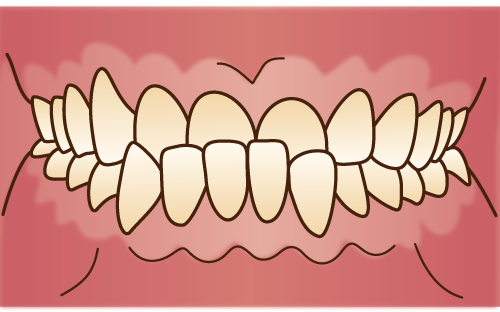

過蓋咬合(上顎前突)

上顎前突

○上顎の過成長、または、下顎が上顎に対して後方に移動している状態

過蓋咬合

○上顎前歯が下顎前歯に垂直的に深く咬み合っている状態。

○上顎前歯が下顎前歯の2/3以上被っている状態

○指しゃぶりや吸唇癖などの口腔習癖や、おしゃぶりの常用による。○口呼吸(鼻づまり)による。○遺伝的な場合がある。 |